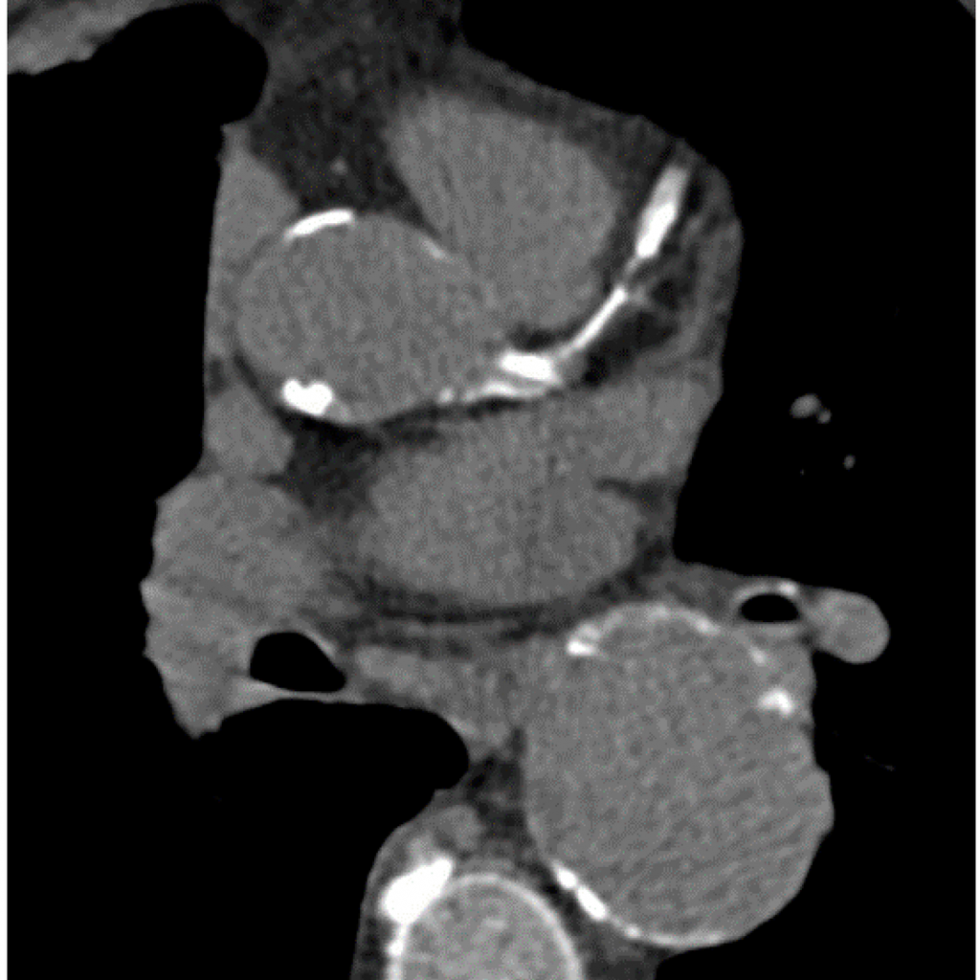

Coronary calcification occurs when calcium deposits in your blood vessels. Research shows that the amount of calcification is directly related to the amount of plaque in your arteries. This plaque increases your likelihood of developing heart disease.

CT scans can detect the amount of calcium build-up in the coronary arteries. The test, otherwise known as a cardiac score, is used to help diagnose heart disease. Because heart disease is a leading cause of death, it is important to undergo screenings. CT scans are one of the most accurate ways to detect calcium build-up in your coronary arteries.